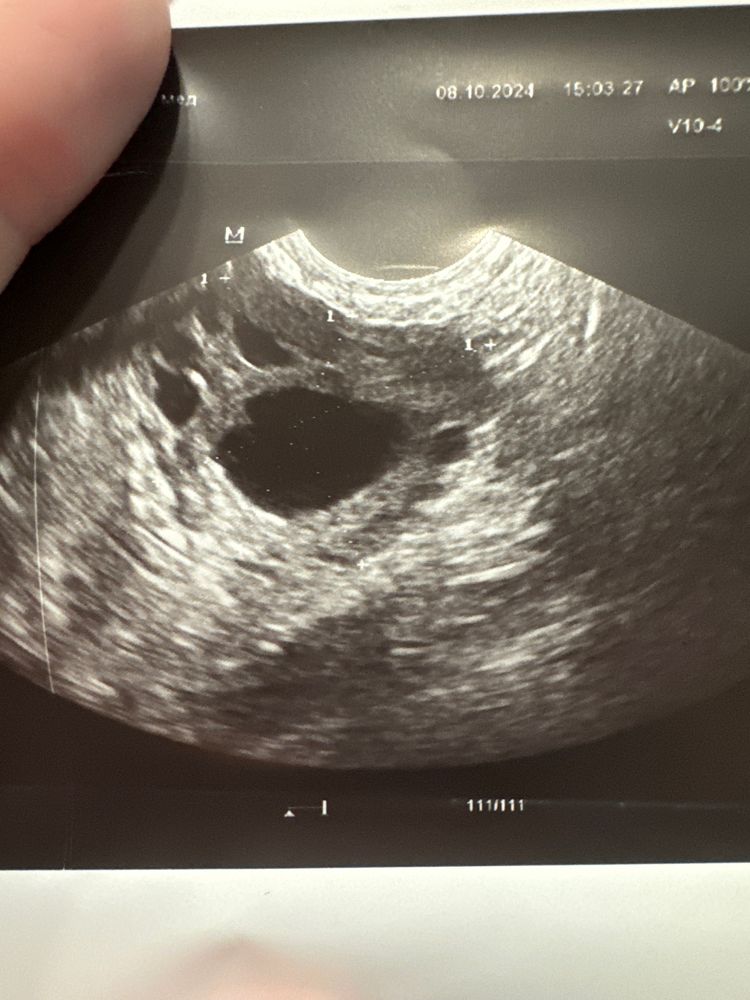

Снова разглядываю свое узи. Фолликул такой странной формы уже. 19 дц, слева 21 мм. Говорили вчера, что «овуляция сегодня-завтра». Смущают такие края неровные.. может овуляция после узи была? Или сегодня? Как думаете? Пик лг на тестах не поймала.. но я его никогда не ловила, даже когда было уже жт.